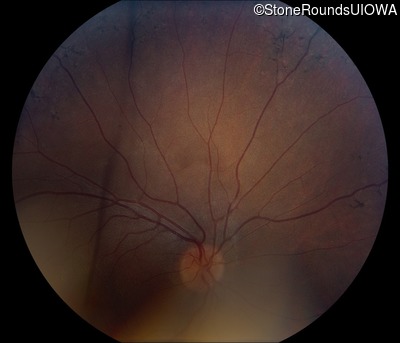

Fundus Photography - Right - 20/40 -1

Exemplar